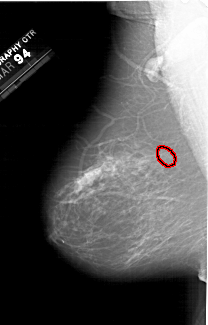

A_1300_1.LEFT_MLO

LEFT_MLO LINES 6166 PIXELS_PER_LINE 3946 BITS_PER_PIXEL 12 RESOLUTION 43.5 OVERLAY

FILE: A_1300_1.LEFT_MLO.OVERLAY

TOTAL_ABNORMALITIES 1

ABNORMALITY 1

LESION_TYPE CALCIFICATION TYPE PUNCTATE-AMORPHOUS DISTRIBUTION CLUSTERED

ASSESSMENT 4

SUBTLETY 4

PATHOLOGY BENIGN

TOTAL_OUTLINES 1

BOUNDARY